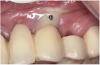

Manifestations of acute infection include abscess and cellulitis. Abscess is an accumulation of pus in an enclosed space7 (Figure 1), while cellulitis is a diffuse inflammatory process within tissues, which may manifest edema, redness, pain, and interference with function (Figure 2). With cellulitis, the infection may be caused by various organisms, and it typically occurs in loose tissues beneath the skin or mucous membranes or around muscle bundles or surrounding organs.7 Also with cellulitis, the severity of the infection is initially determined by virulence of invading bacteria and the host’s response.

A periodontal abscess usually manifests itself as red, painful swelling adjacent to a tooth, where it is typically associated with deep probing depths; a draining fistula is rarely present. In contrast, an endodontic abscess often demonstrates an inflamed fistulous tract, which is typically apical to the mucogingival junction. In a radiograph, there often is radiolucency at the apex of the tooth.

Figure 1 Fistulous tract at tooth No. 30 associated with an endodontic-periodontal abscess. When palpated, the fistulous tract may express pus. Usually, a periodontal abscess will not have a fistulous tract. Its appearance usually reflects an endodontic etiology causing the lesion. (Photograph courtesy of Dr. Mehmet Dikman.)

Figure 1